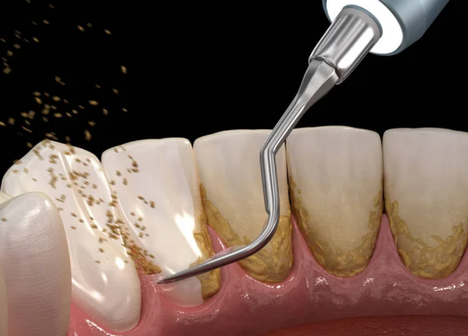

Tecnologia de Ultrassom

Esqueça o desconforto das limpezas antigas. Utilizamos vibrações ultrassônicas de alta precisão que removem o tártaro sem agredir os tecidos moles. Protege suas gengivas, reduz o sangramento e torna o tratamento periodontal muito mais tranquilo!

• Conforto e Tecnologia Ultrassônica: O tratamento periodontal não precisa ser doloroso. Utilizamos Ultrassom Piezoelétrico, que remove o tártaro através de vibrações precisas e irrigação, sendo muito mais gentil e confortável do que as raspagens manuais antigas.

Não. Na Odontologia Velasco, o conforto do paciente é prioridade. Utilizamos anestesia local sempre que necessário, garantindo que você não sinta dor durante o procedimento. Além disso, utilizamos tecnologias como o Ultrassom Piezoelétrico, que remove o tártaro através de vibrações sônicas delicadas e irrigação morna, tornando o pós-operatório muito mais tranquilo.